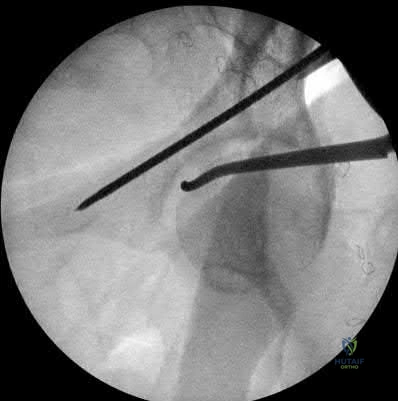

A 25-year-old male is brought to the emergency department after a high-speed motorcycle collision. He is hemodynamically unstable. A pelvic binder is appropriately placed. Radiographs reveal a rotationally unstable but vertically stable pelvic ring injury with symphyseal widening greater than 2.5 cm (APC-II pattern). Which of the following ligaments is predominantly disrupted at the sacroiliac joint in this specific injury pattern?

An Anteroposterior Compression Type II (APC-II) injury involves diastasis of the pubic symphysis > 2.5 cm, with disruption of the anterior sacroiliac, sacrotuberous, and sacrospinous ligaments. The posterior sacroiliac ligaments remain intact, maintaining vertical stability. Thus, at the sacroiliac joint, the anterior sacroiliac ligament is the one disrupted.